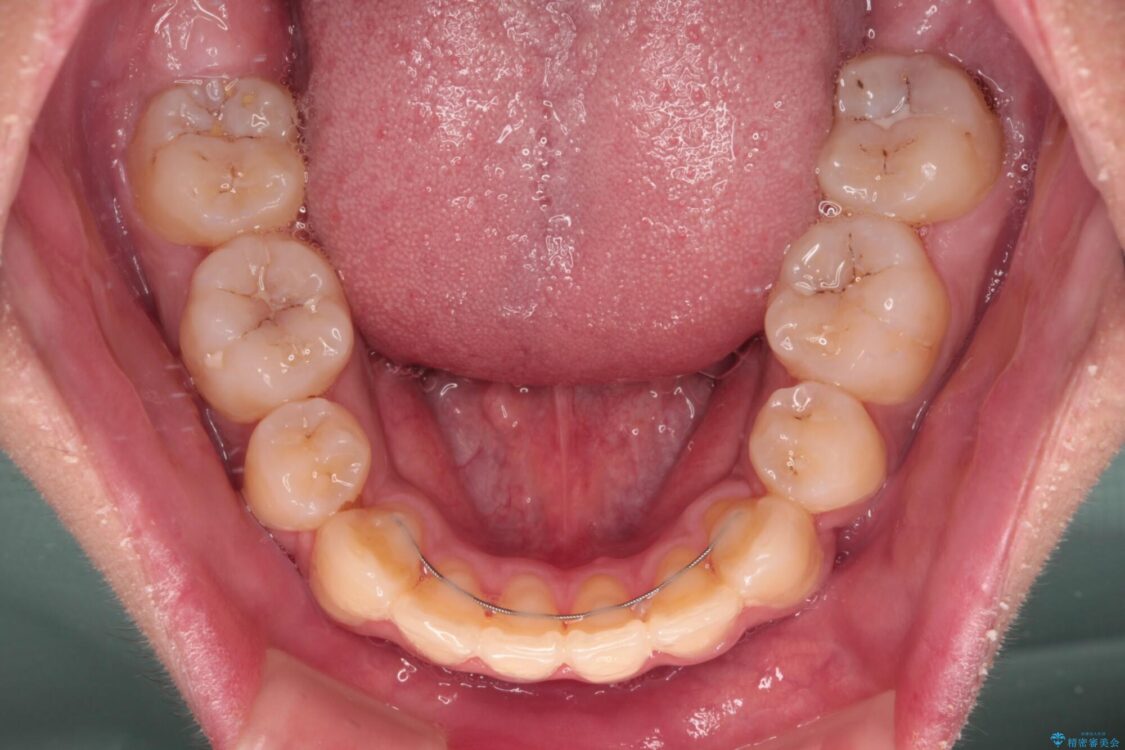

治療途中

• 膨らんだ口元 ワイヤー装置での抜歯矯正 治療途中画像